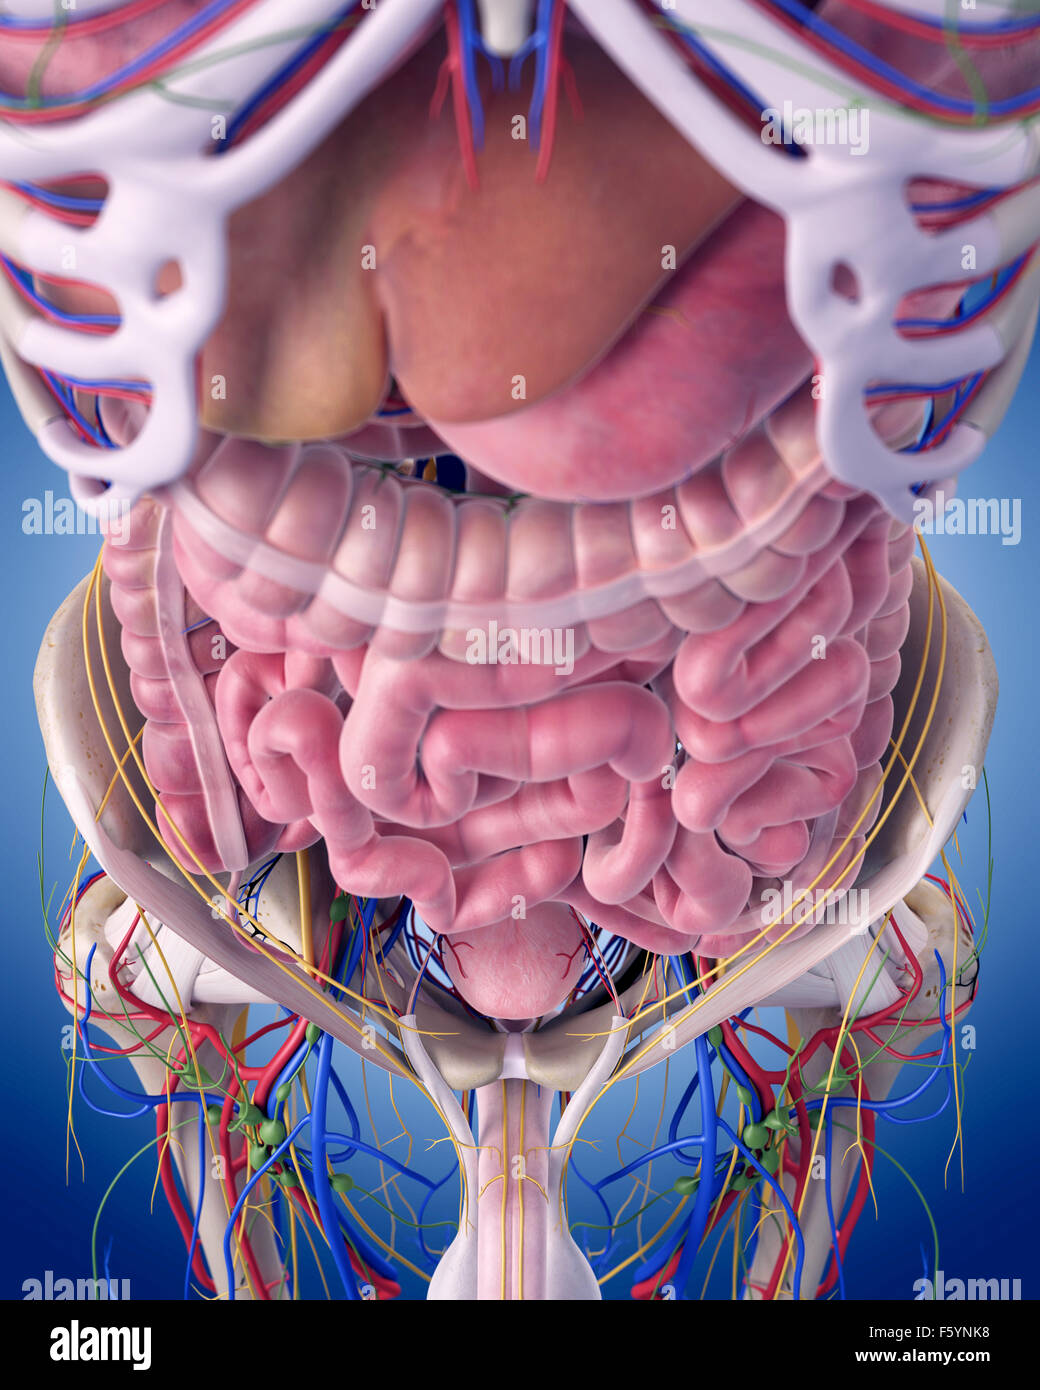

schematicfixblagged.z22.web.core.windows.netMale Abdominal Organs, Computer Illustration Stock Photo - Alamy

schematicfixblagged.z22.web.core.windows.netMale Abdominal Organs, Computer Illustration Stock Photo - Alamy

Male Abdominal Organs, Computer Illustration Stock Photo - Alamy

Male Abdominal Organs #1 Photograph By Sebastian Kaulitzki/science

fineartamerica.comorgans abdominal kaulitzki

fineartamerica.comorgans abdominal kaulitzki